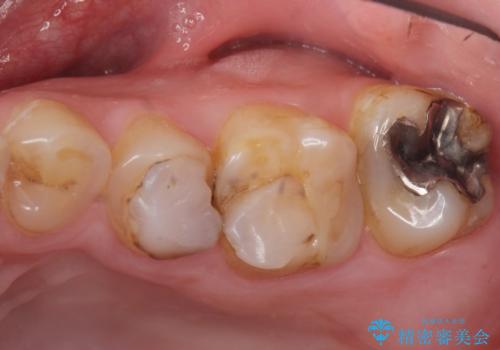

- K-POP(Kポップ)アイドルのような歯にしたいと希望され来院された患者様です。

矯正を途中でやめてしまったとのことで、歯に矯正の接着材が残っており着色も顕著でした。

奥歯の咬合面にはレジンが盛られた状態でした。

見た目と咬み合わせを改善するため、セラミッククラウンによる治療を行いました。